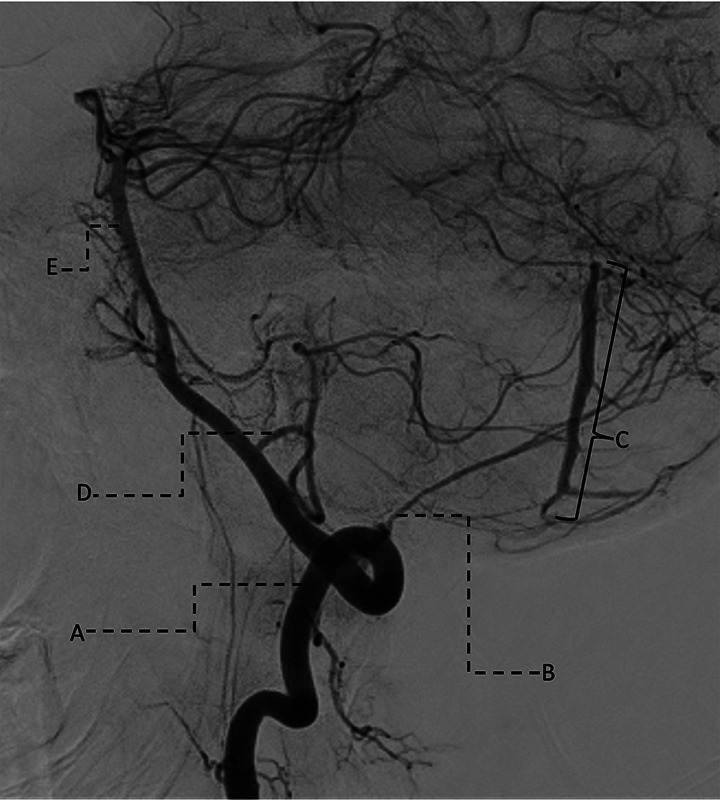

We report the case of a 45-year-old man with a rare cerebellar dural arteriovenous fistula (dAVF) presenting with dizziness and gait imbalance. MRI revealed a hemorrhagic lesion compressing the fourth ventricle. Digital subtraction angiography confirmed a Borden Type III dAVF, which was successfully treated by balloon-assisted embolization using PHIL 25%. This case draws attention to the importance of early diagnosis and intervention in posterior fossa dAVFs. Teaching point: Cerebellar dAVFs, though rare, harbor a high risk of hemorrhage and require prompt imaging and endovascular treatment.